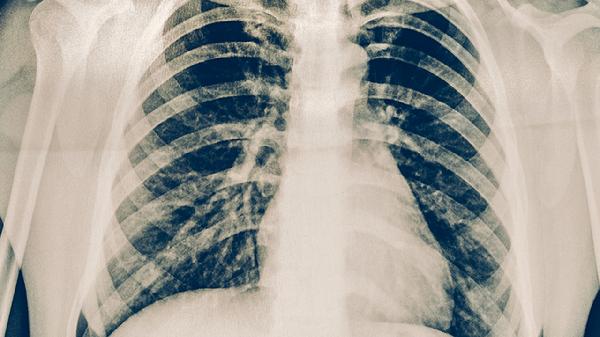

肺结核患者痰涂片可能检出抗酸杆菌,结核菌素试验及γ-干扰素释放试验呈阳性,胸部影像学可见典型结核病灶。普通发热患者血常规可能显示白细胞升高或正常,病原学检查可明确具体感染源。